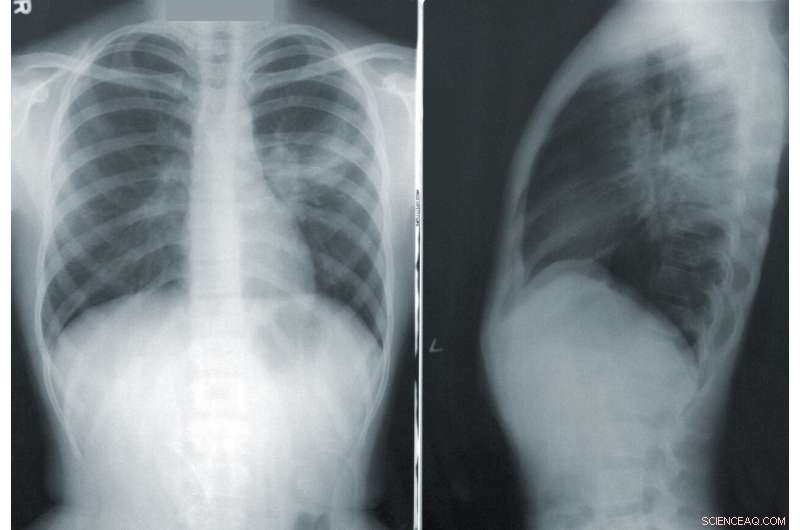

X-Ray showing pneumonia. Credit: CDC on Unsplash

New research using machine learning on images of everyday items is improving the accuracy and speed of detecting respiratory diseases, reducing the need for specialist medical expertise.

Results of this technique, known as transfer learning, achieved a 99.24 percent success rate when detecting COVID-19 in chest X-rays.

"Our technique has the capacity to not only detect COVID-19 in chest X-rays, but also other chest diseases such as pneumonia. We have tested it on 10 different chest diseases, achieving highly accurate results," he said.